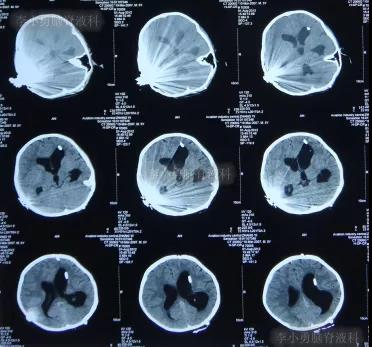

一到第3家医院,就开展了急诊气管插管和之后呼吸机辅助呼吸的抢救。住院次日,即2012年5月17日,脑CT检查并未发现明显异常(图-3)。

图-3:2012年5月17日耳蜗植入术后状态脑CT

住院3天根据腰椎穿刺脑脊液化验结果,确诊为肺炎链球菌脑膜炎,之后针对此细菌性脑膜炎的给以抗生素调整性治疗。